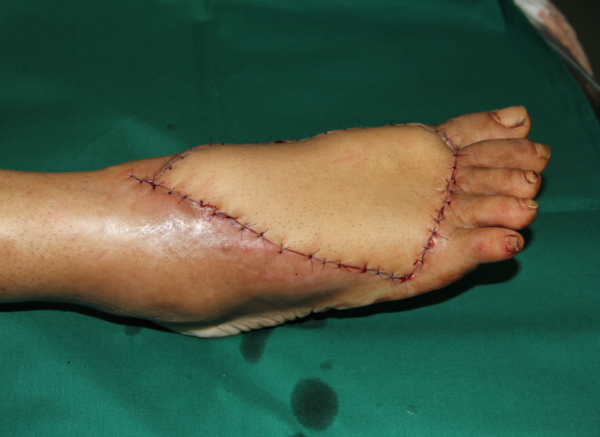

玉米机伤右足复合组织缺损,腓骨皮瓣修复,术后12天,伤口愈合良好,今日出院清创后

术中

跖趾关节成形

术后即刻

术后12天,没有感染